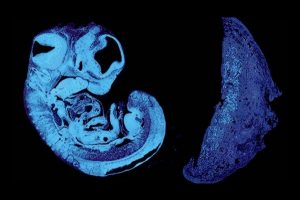

Cinsiyetler Savaşının Anne Karnında Başladığı Ortaya Çıktı Bilim insanları, anne ve babanın fetüse aktardığı genlerin gebelik sırasında çetin bir rekabete